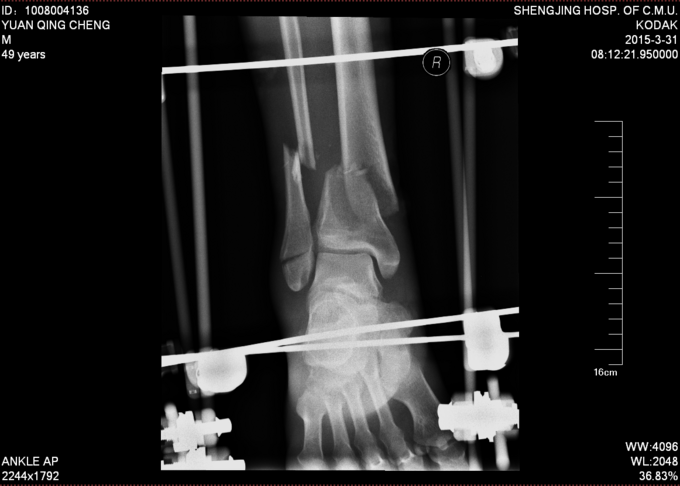

诊断:左胫腓骨远端开放性粉碎性骨折 患者车祸入院后行行抗炎消肿止疼等对症治疗后约一周,局部皮肤软组织条件差,局部皮肤全层坏死,行左胫腓骨远端外固定架固定术。

患者皮肤条件差,行外固定架维持患肢长度,如果直接行内固定治疗,切口处易感染,危险。